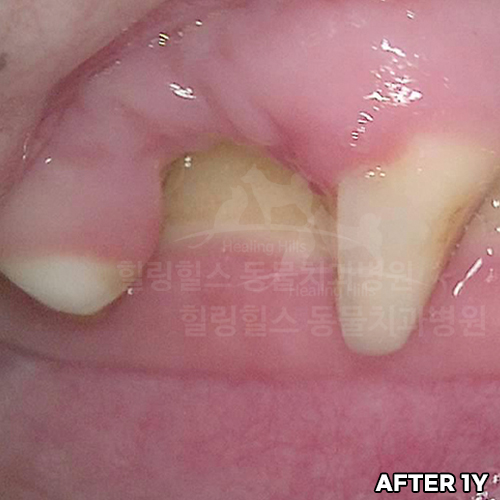

웰시코기의 아주 심한 파절치아를 강아지치과에서 수술하고 1년 뒤에도 잘 씹어요~!! - 동물치과 힐링힐스 -